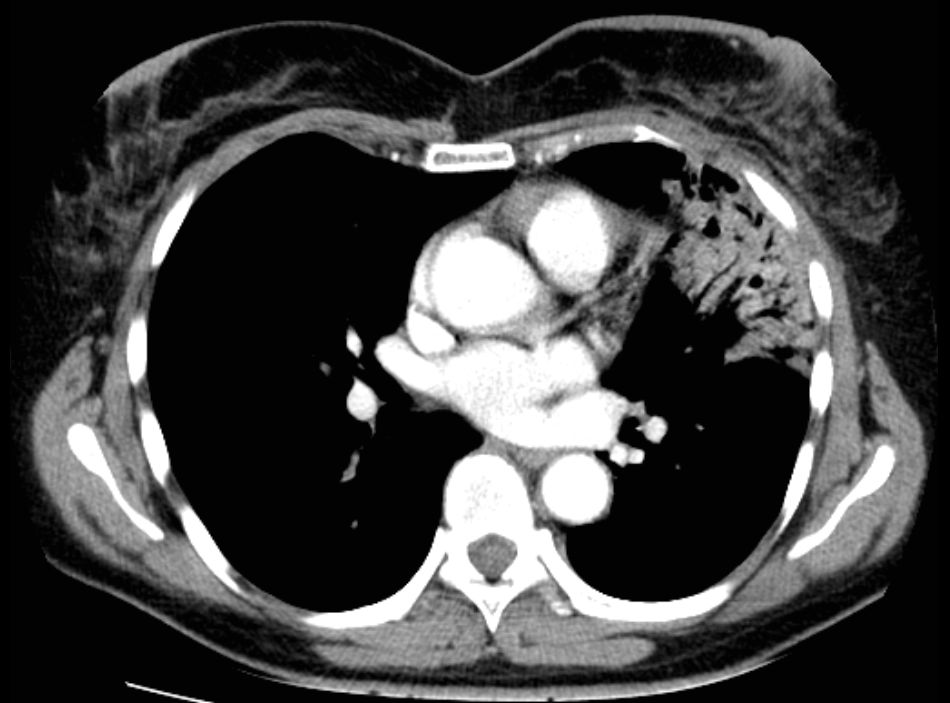

Pneumonitis 53-jährige Frau mit Mammakarzinom links. 3 Monate nach brusterhaltender Therapie und Bestrahlung der Brust wird die Patientin wegen einer Pneumonie ins Krankenhaus eingewiesen. Nach Gabe von Antibiotika zunächst nur geringe Besserung.

Das Thoraxbild zeigt ein Infiltrat im linken Mittelfeld.

Das CT zeigt eine Anschoppung direkt unter der bestrahlten Brust. Negatives Bronchogramm gut erkennbar.

Durch ein leichte Trichterbrust war ungewöhnlich viel Lungenparenchym in der Tangente bestrahlt.